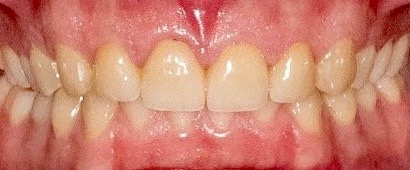

Fig 20. Final outcome after delivery of cantilevered FPDs for teeth Nos. 7, 10, and 22.

Figure 20

Digital impressioning and digitally driven treatment planning and execution are quickly becoming the norm in orthodontic treatment. This allows for interdisciplinary treatment to be performed digitally, even in the presence of brackets and wires. As an example, a 13-year-old patient presented with congenitally missing maxillary lateral incisors, as well as tooth No. 22. After discussing various treatment options, the patient and her parents decided to maintain the edentulous spaces with resin-bonded fixed partial dentures (RBFPDs) until the patient was old enough for dental implants. At completion of orthodontic treatment but before removal of brackets and wires, the patient was digitally scanned (Figure 18). Her models were manipulated in orthodontic software to remove the brackets, and the case was imported into restorative CAD software for design and fabrication of the RBFPDs (Figure 19). The e.max RBFPDs were milled and subsequently delivered immediately after bracket removal (Figure 20).